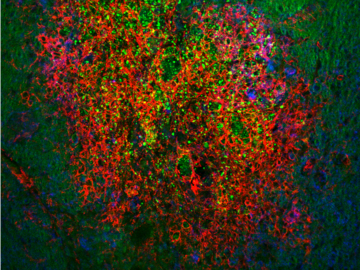

Striking Laboratory Data Images

Laboratory Data Gallery

Universe of the brain